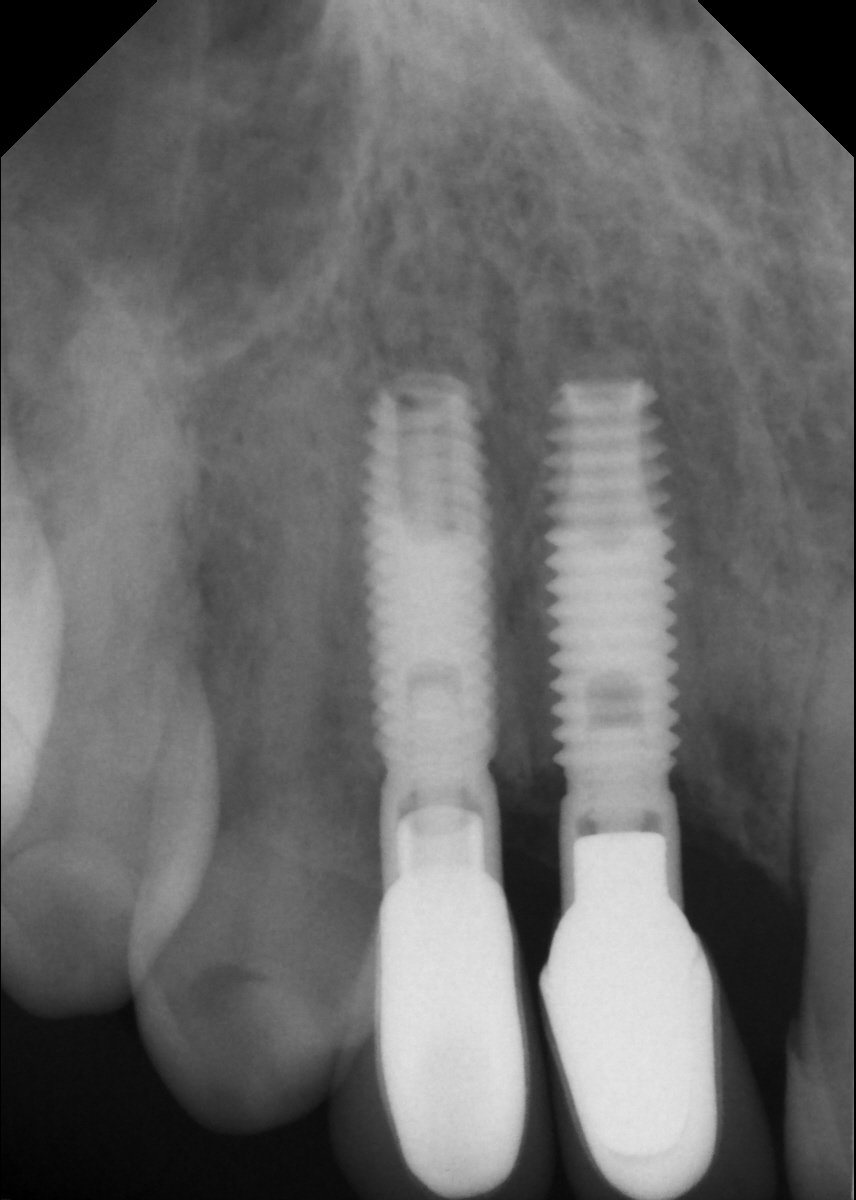

Necesito saber que marca de implantes son los dos de la derecha. Gracias

Buenas Noches: Me gustaría saber qué tipos de implantes son estos, para poder rehabilitarlos Gracias